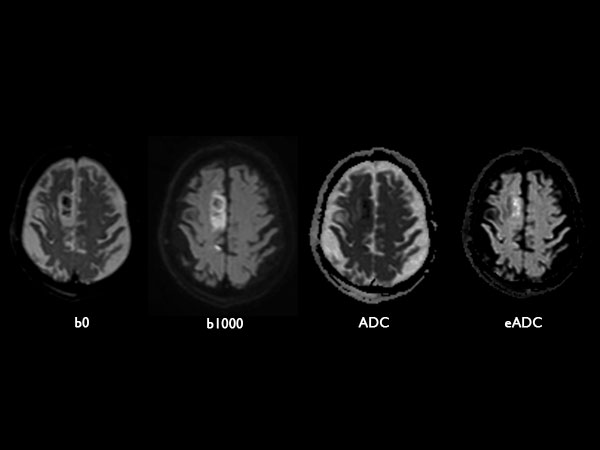

Acute stroke. Patient was brought to the first aid and directly transferred to the MRI unit. Axial studies were performed to get an overview of the stroke. Total study time is 9 minutes.

Diffusion